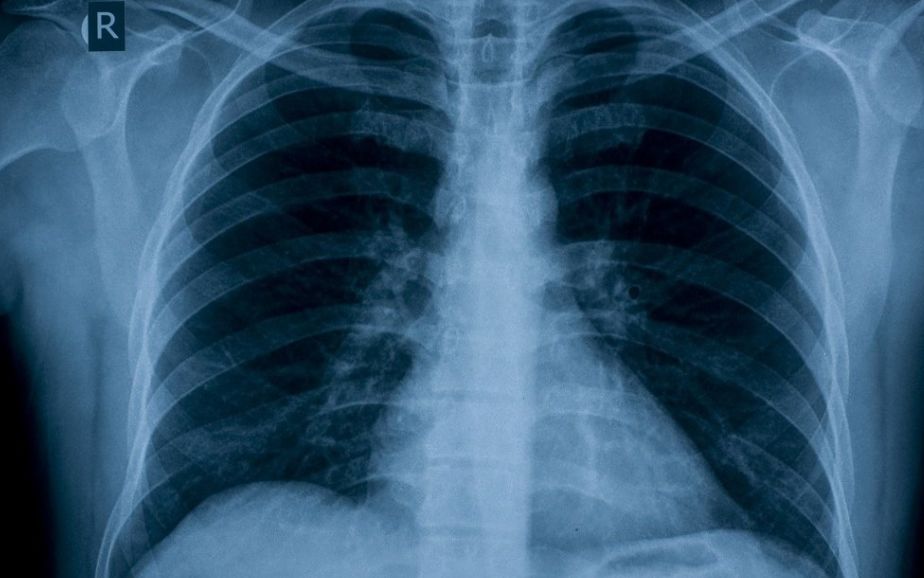

今天,全世界大概有10亿人患有高血压,

这意味着成年人中每四个人中就有一个患有高血压。

高血压普遍存在于发展中国家以及发达国家。

长期缺乏控制或治疗不足的高血压是

心脏病发作、中风、肾功能衰竭

和其它心血管疾病发生的一个重大的风险因素。